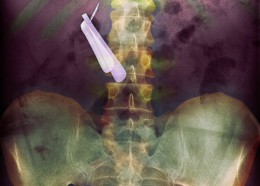

Чудни ренгенски снимки